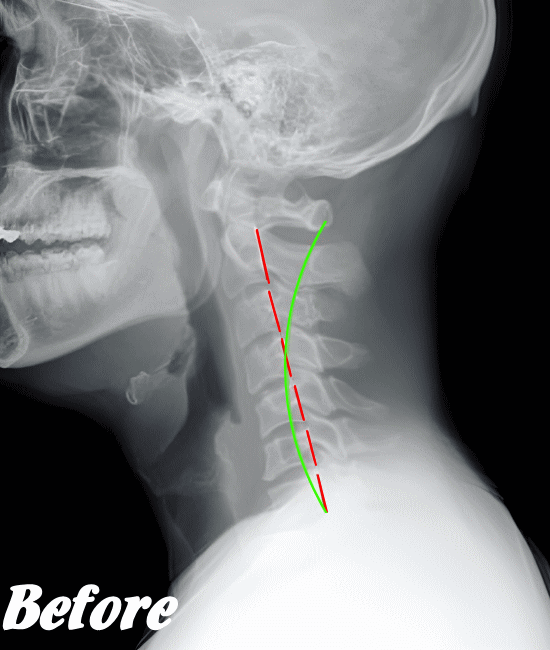

緊張型頭痛/肩こり頭痛の発生は、首背面の筋肉が緊張し血流が悪くなることが大きな原因だと考えられます。そこで、まずは首まわりや肩まわりの筋肉を緩め、潤滑な血行を確保させることを優先に施術します。

そのために、背骨の歪みを整え、肋骨、肩甲骨、首や首の付け根など、血流を阻害している部位の筋骨格をすべて調整します。